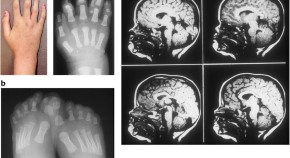

Primary cilia are hair-like, non-motile sensory organelles that are found on the surface of almost all cells in vertebrates. Defects in these organelles can lead to a wide array of disorders known as ciliopathies. In this Review, Valente et al. focus on ciliopathies with major neurological involvement, describing their clinical features and known pathogenetic mechanisms, and discussing the possible aetiologies of associated brain malformations.